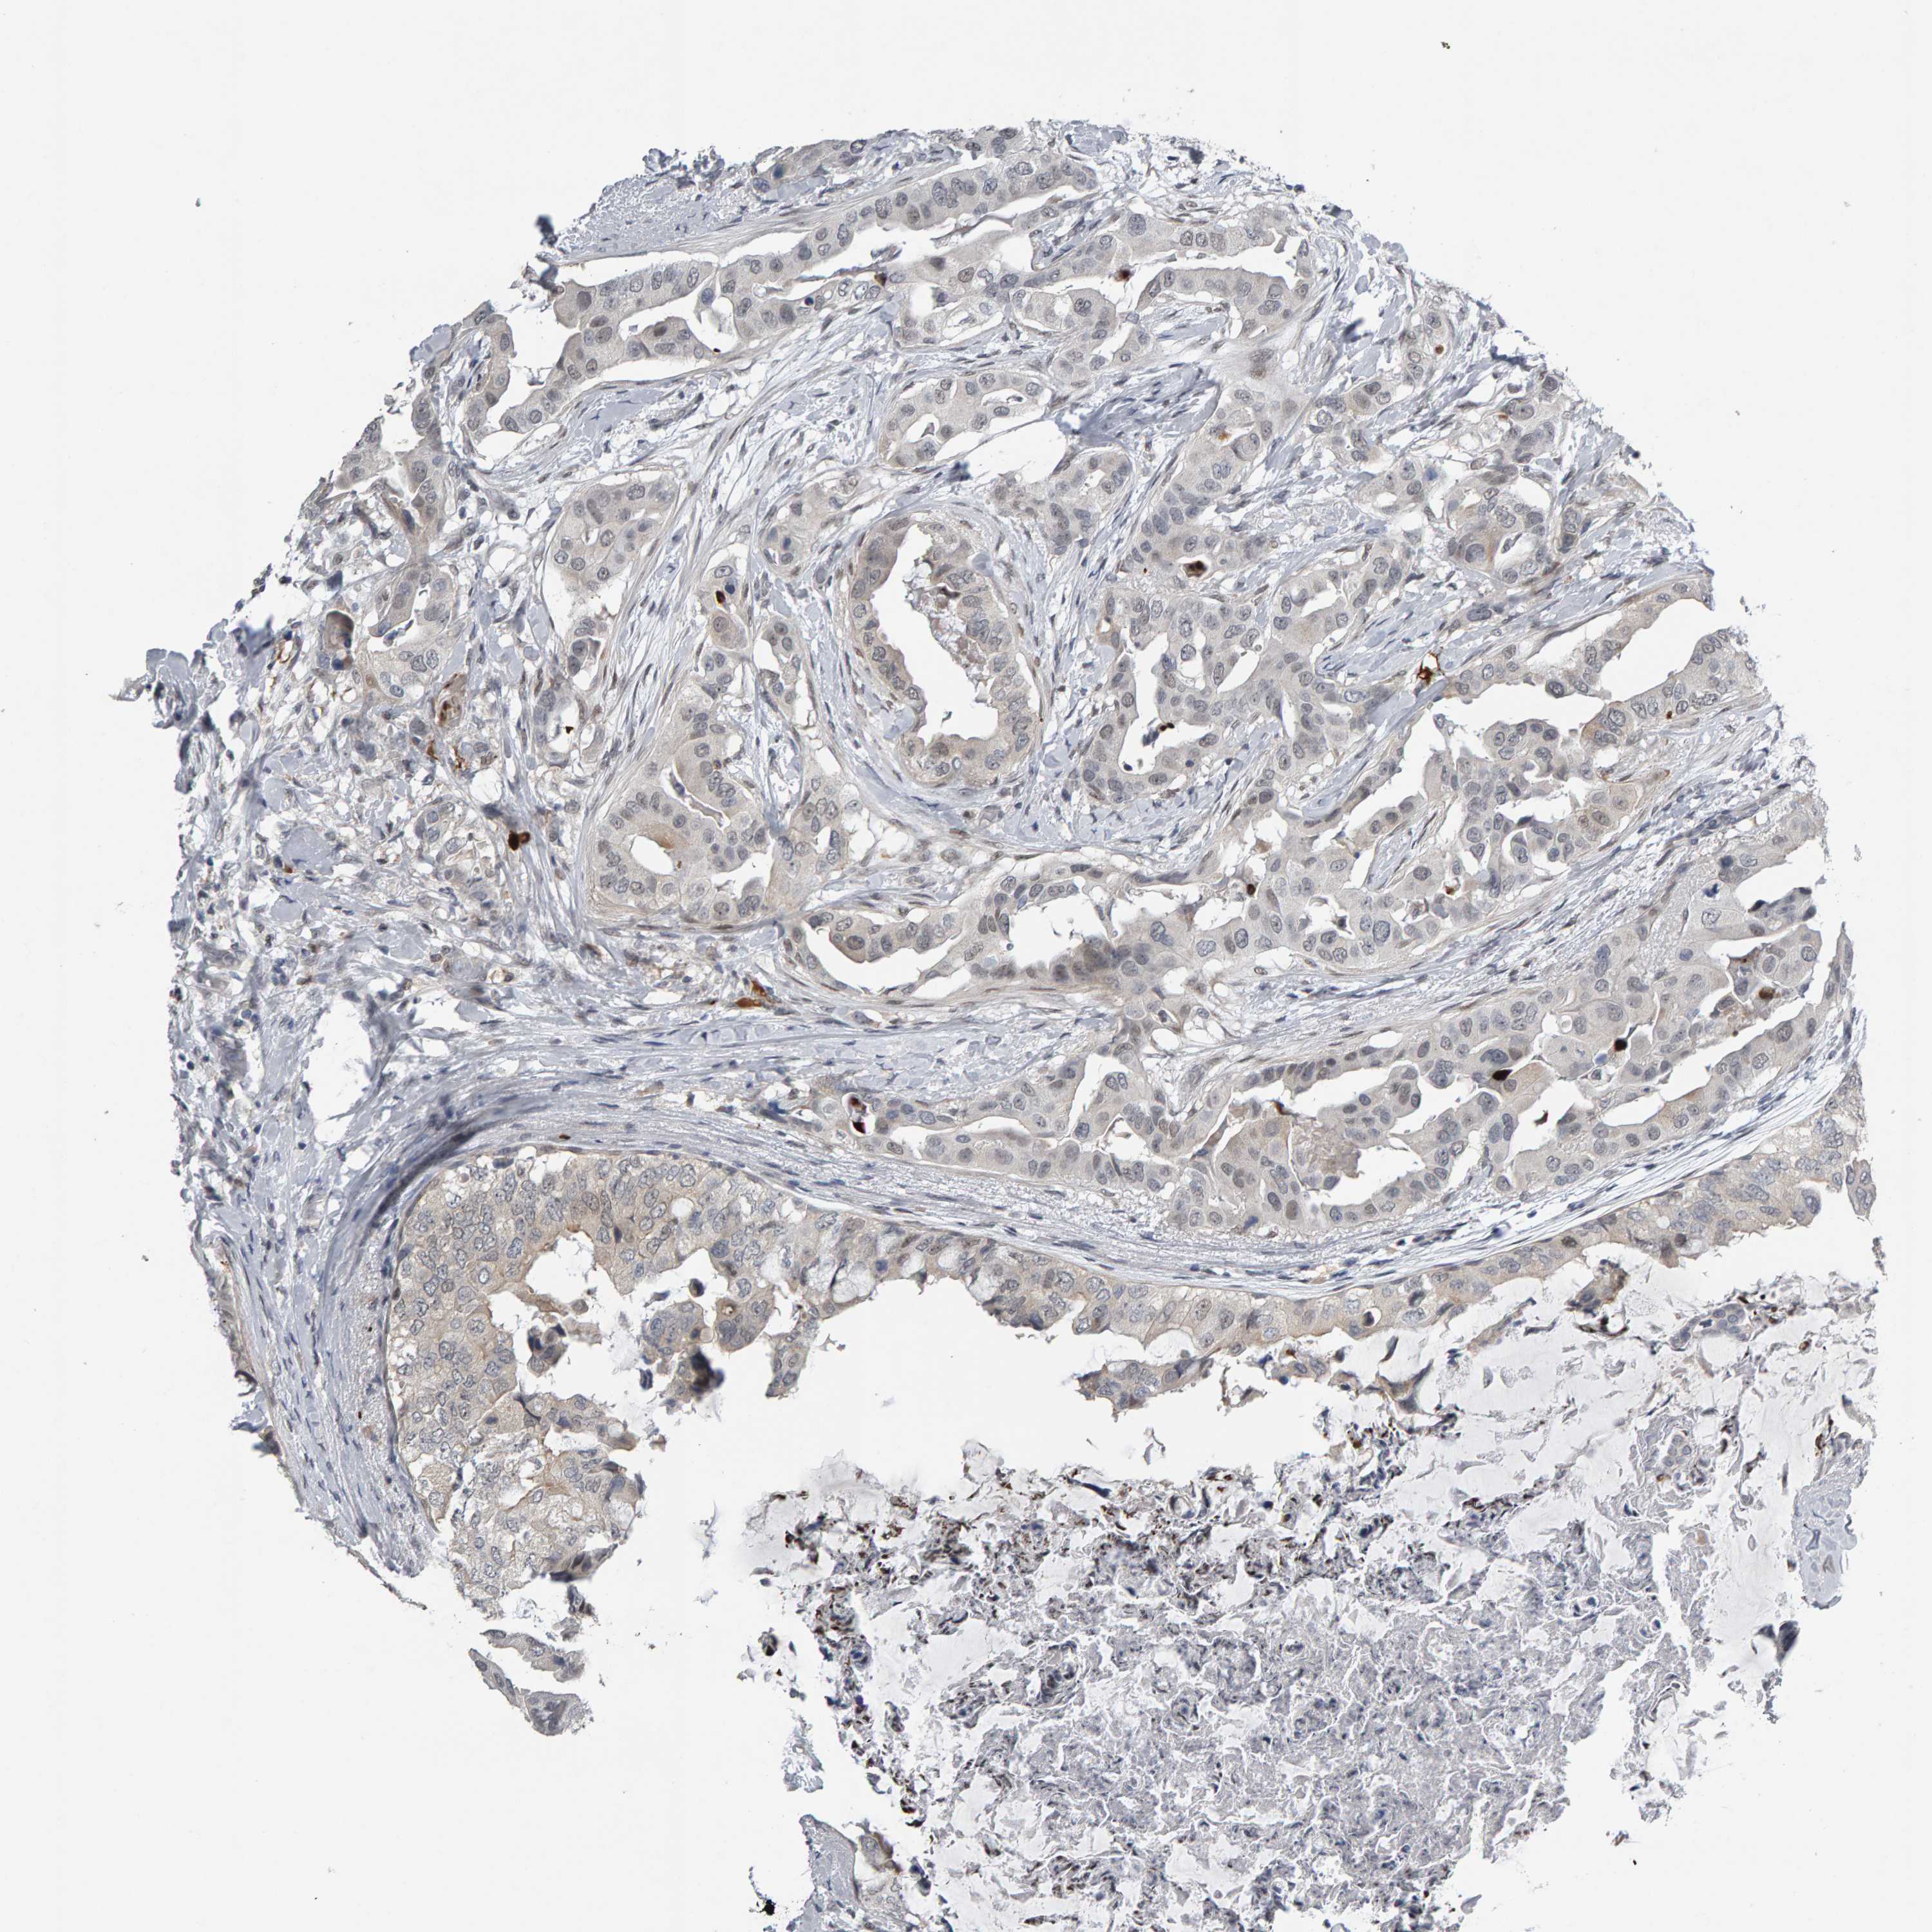

CANCER BREAST CANCER Show tissue menu

BRCA TCGA BRCA VALIDATION PROTEIN EXPRESSION